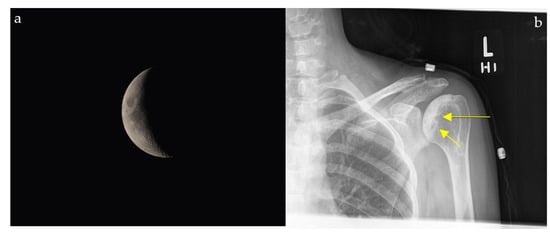

2.4. Loss of Half-Moon Overlap Sign

2.11. Crescent Sign

2.11.2. On Conventional Radiographs

2.13. Lateral Crescent Sign